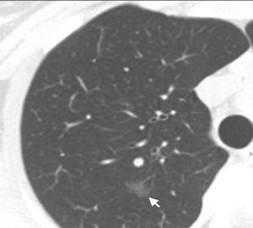

(Слева) На аксиальной КТ с КУ у женщины 37 лет с отеком легких определяется ровное утолщение междольковых перегородок. Отек позволяет различить полигональные границы вторичных легочных долек в базальных отделах легкого. Обратите внимание на хорошо заметные центральные дольковые артерии на фоне утолщения центрилобулярно-го интерстиция.

(Справа) На корональной КТ с КУ у этой же пациентки на периферии средней доли визуализируются вторичные легочные дольки, окруженные толстыми междольковыми перегородками. (Слева) На аксиальной КТ с КУ у мужчины 68 лет с метастатическим раком предстательной железы и лимфотенным канцеро-матозом определяется нодулярное утолщение междольковых пе регородок, незначительный плевральный выпот справа видны также разбросанные мелкие узелки в легких (гематогенные метастазы).

(Справа) На корональной КТ с КУ у этого же пациента определяется нодулярное утолщение междольковых перегородок вокруг многих вторичных легочных долек. Обратите внимание на асимметричный характер поражения с сохранностью некоторых участков, характерный для лимфогенного канцероматоза. (Слева) На аксиальной КТВР у женщины 59 лет с саркоидозом визуализируются сгруппированные перилимфатические микроузелки с обеих сторон на фоне нодулярного утолщения некоторых междольковых перегородок. Некоторые септальные микроузелки очерчивают края вторичных легочных долек.

(Справа) На аксиальной КТВР у женщины 74 лет с интерстициальным легочным фиброзом определяется неравномерное утолщение некоторых междольковых перегородок в сочетании с тракционными бронхо- и бронхиолоэктазами.

(Слева) На аксиальной КТВР у курильщика 45 лет с диспноэ определяются диффузные центрилобулярные участки снижения пневматизации по типу «матового стекла», сопоставимые с респираторным бронхиолитом, ассоциированным с интерстициаль ным заболеванием легких. Тонкая «полоска» сохранной ткани легкого в субплевральных отделах сопоставима с центрилобулярной локализацией изменений.

(Справа) На аксиальной КТ с КУ (,MIP) у женщины 34 лет с инфекционным бронхиолитом визуализируются очаги в виде «дерева в почках», расположенные в центральных отделах вторичных легочных долек, окруженных неизмененной легочной паренхимой. (Слева) На аксиальной КТВР у мужчины-курильщика 58 лет определяются признаки центри-лобулярной эмфиземы в виде множественных участков повышения пневматизации с дольковыми артериями в центре, выглядящими как точки.

(Справа) На аксиальной КТ без КУ у женщины 46 лет с пневмонией, вызванной золотистым стафилококком, визуализируются множественные очаги повышенной плотности по типу «матового стекла» и консолидации. Картина характерна для бронхопневмонии. (Слева) На аксиальной КТВР у фермера с гиперчувствительным пневмонитом определяется т.н. симптом «зельца», проявляющийся повышением пневматизации одних легочных долек (за счет воздушных «ловушек») и снижением пневматизации других долек по типу «матовою стекла» на фоне неизмененной легочной паренхимы.

(Справа) На аксиальной КТ без КУ у женщины 24 лет с организующейся пневмонией визуализируются характерные участки консолидации на периферии легочных долек. Определяются также симптомы обратного гало и атолла. Относительно сохранные вторичные легочные дольки окружены зонами консолидации.